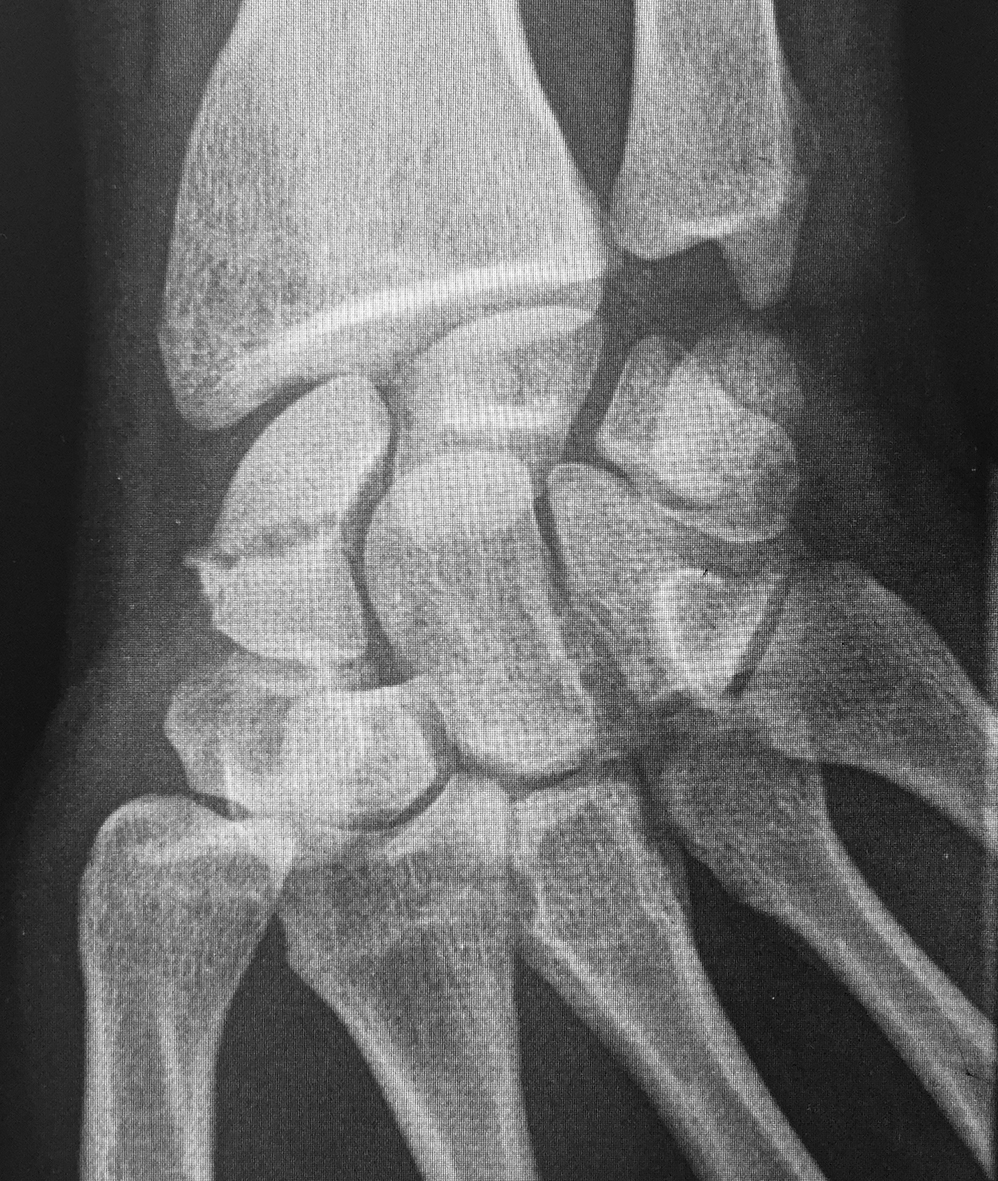

Figura 4: Caso 12

a) Radiografía de frente pre-operatoria

b) Radiografía pre-opertaoria, enfoque de escafoides

c) Radiografía post operatoria

e) 24 meses de seguimiento. Radiografía de frente

f) 24 meses de seguimiento. Radiografía de perfi